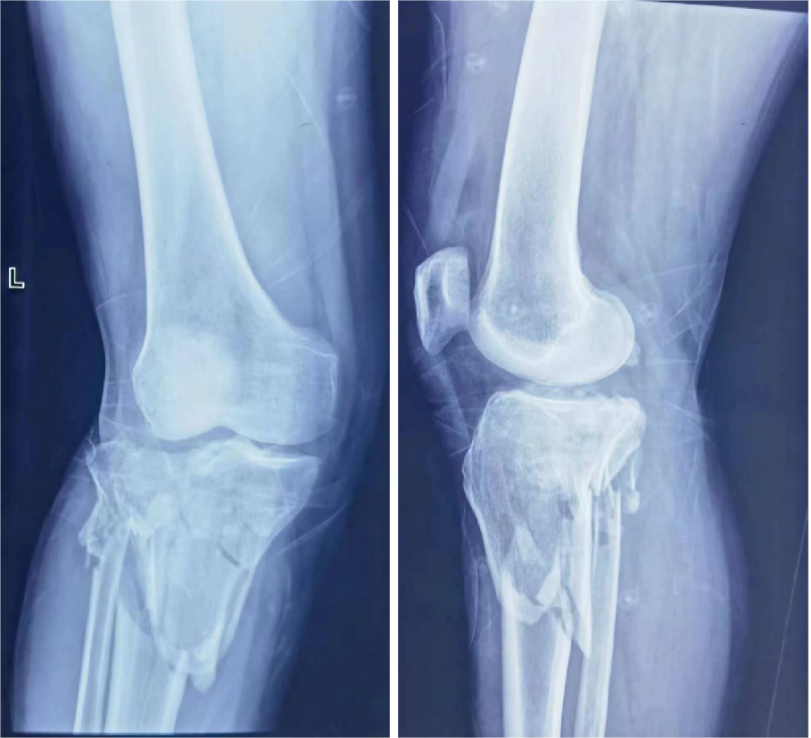

为深入贯彻党的二十大精神和习近平总书记关于深化东西部协作,落实“京蒙协作-医疗倍增计划”以及“公立医院高质量发展重点专科建设项目”,提升我院创伤急救外科水平,8月11日,我院特邀北京积水潭医院著名创伤外科专家刘亚波教授来院交流并进行复杂胫骨平台粉碎型骨折手术的演示指导。胫骨平台骨折手术一直以来是骨科手术中比较棘手的技术难题,治疗效果不太理想。通过刘亚波教授的手术演示、临床经验以及学术成果的分享,使我们对复杂胫骨平台手术以及创伤急救有了更广阔的发展思路。

患者X光片